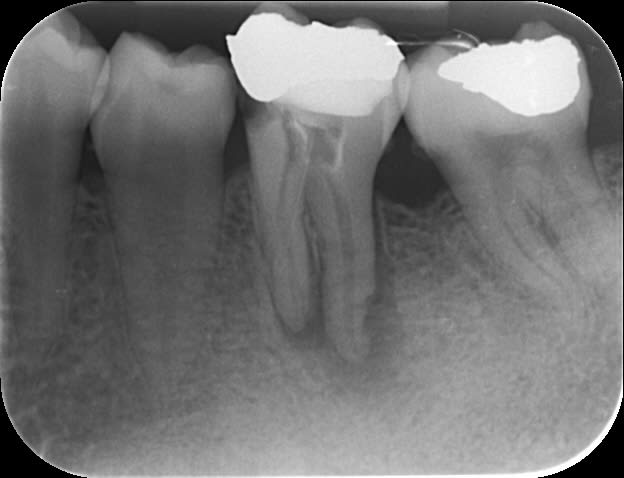

mrquentin

il fallait bien que je me vante auprès de quelqu'un!!! je me suis pris pour le roi du monde pdt 5 minutes ;)

au début je me suis dis: "c'est une fracture ce trait?" sur la radio préop?

cond lat à froid+thermocompactage.